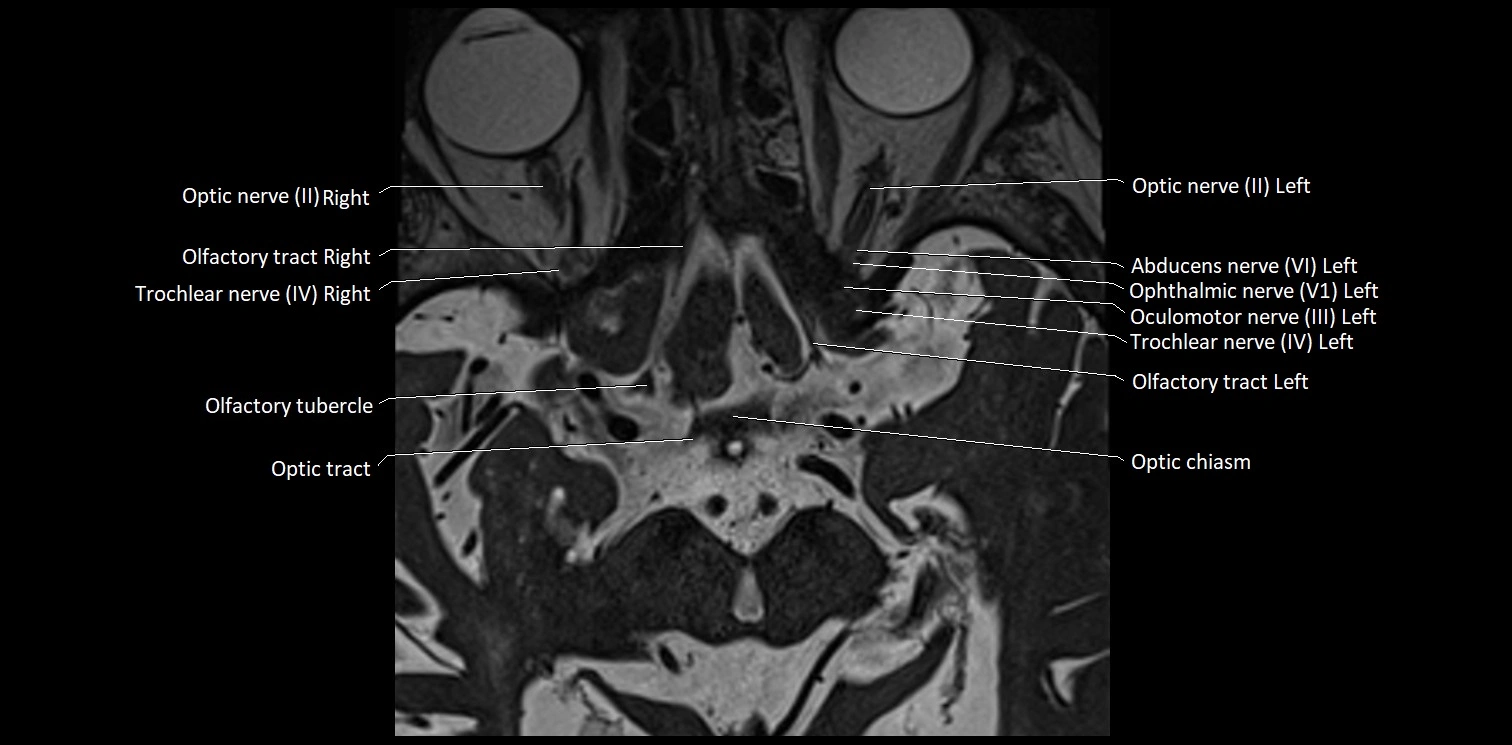

MRI Appearance

• The abducens nerve is a small, thin, linear structure

• Best visualized on high-resolution T2-weighted 3D MRI sequences (e.g., FIESTA or CISS)

• Seen as a hypointense (dark) line running from the brainstem at the pontomedullary junction, traversing the prepontine cistern, and entering Dorello’s canal under the petrosphenoidal ligament, then into the cavernous sinus, and finally the orbit

• May be challenging to visualize in standard MRI due to its small size

• Pathology may be inferred by absence, displacement, or enhancement of the nerve